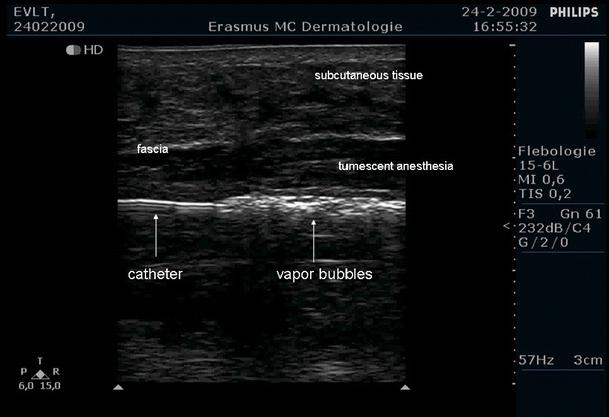

Endovenous laser ablation (EVLA) produces boiling bubbles emerging from pores within the hot fiber tip and traveling over a distal length of about 20 mm before condensing. This evaporation-condensation mechanism makes the vein act like a heat pipe, where very efficient heat transport maintains a constant temperature, the saturation temperature of 100 degrees C, over the volume where these non-condensing bubbles exist. During EVLA the above-mentioned observations indicate that a venous cylindrical volume with a length of about 20 mm is kept at 100 degrees C. Pullback velocities of a few mm/s then cause at least the upper part of the treated vein wall to remain close to 100 degrees C for a time sufficient to cause irreversible injury. In conclusion, we propose that the mechanism of action of boiling bubbles during EVLA is an efficient heat-pipe resembling way of heating of the vein wall.

静脉内激光消融 (EVLA) 会产生从热光纤尖端的孔隙中冒出的沸腾气泡,并在凝结之前沿约 20mm 的远端长度传播。这种蒸发-冷凝机制使静脉像热管一样,其中非常有效的热传递在存在这些不凝气泡的体积内保持恒定温度,即 100 摄氏度的饱和温度。在 EVLA 过程中,上述观察结果表明,一个长度约为 20mm 的静脉圆柱体积保持在 100 摄氏度。以几毫米/秒的后退速度,至少会使处理后的静脉壁的上部在足以引起不可逆转损伤的时间内保持接近 100 摄氏度。总之,我们提出,在 EVLA 过程中,沸腾气泡的作用机制是一种类似于热管壁加热的高效热管方式。